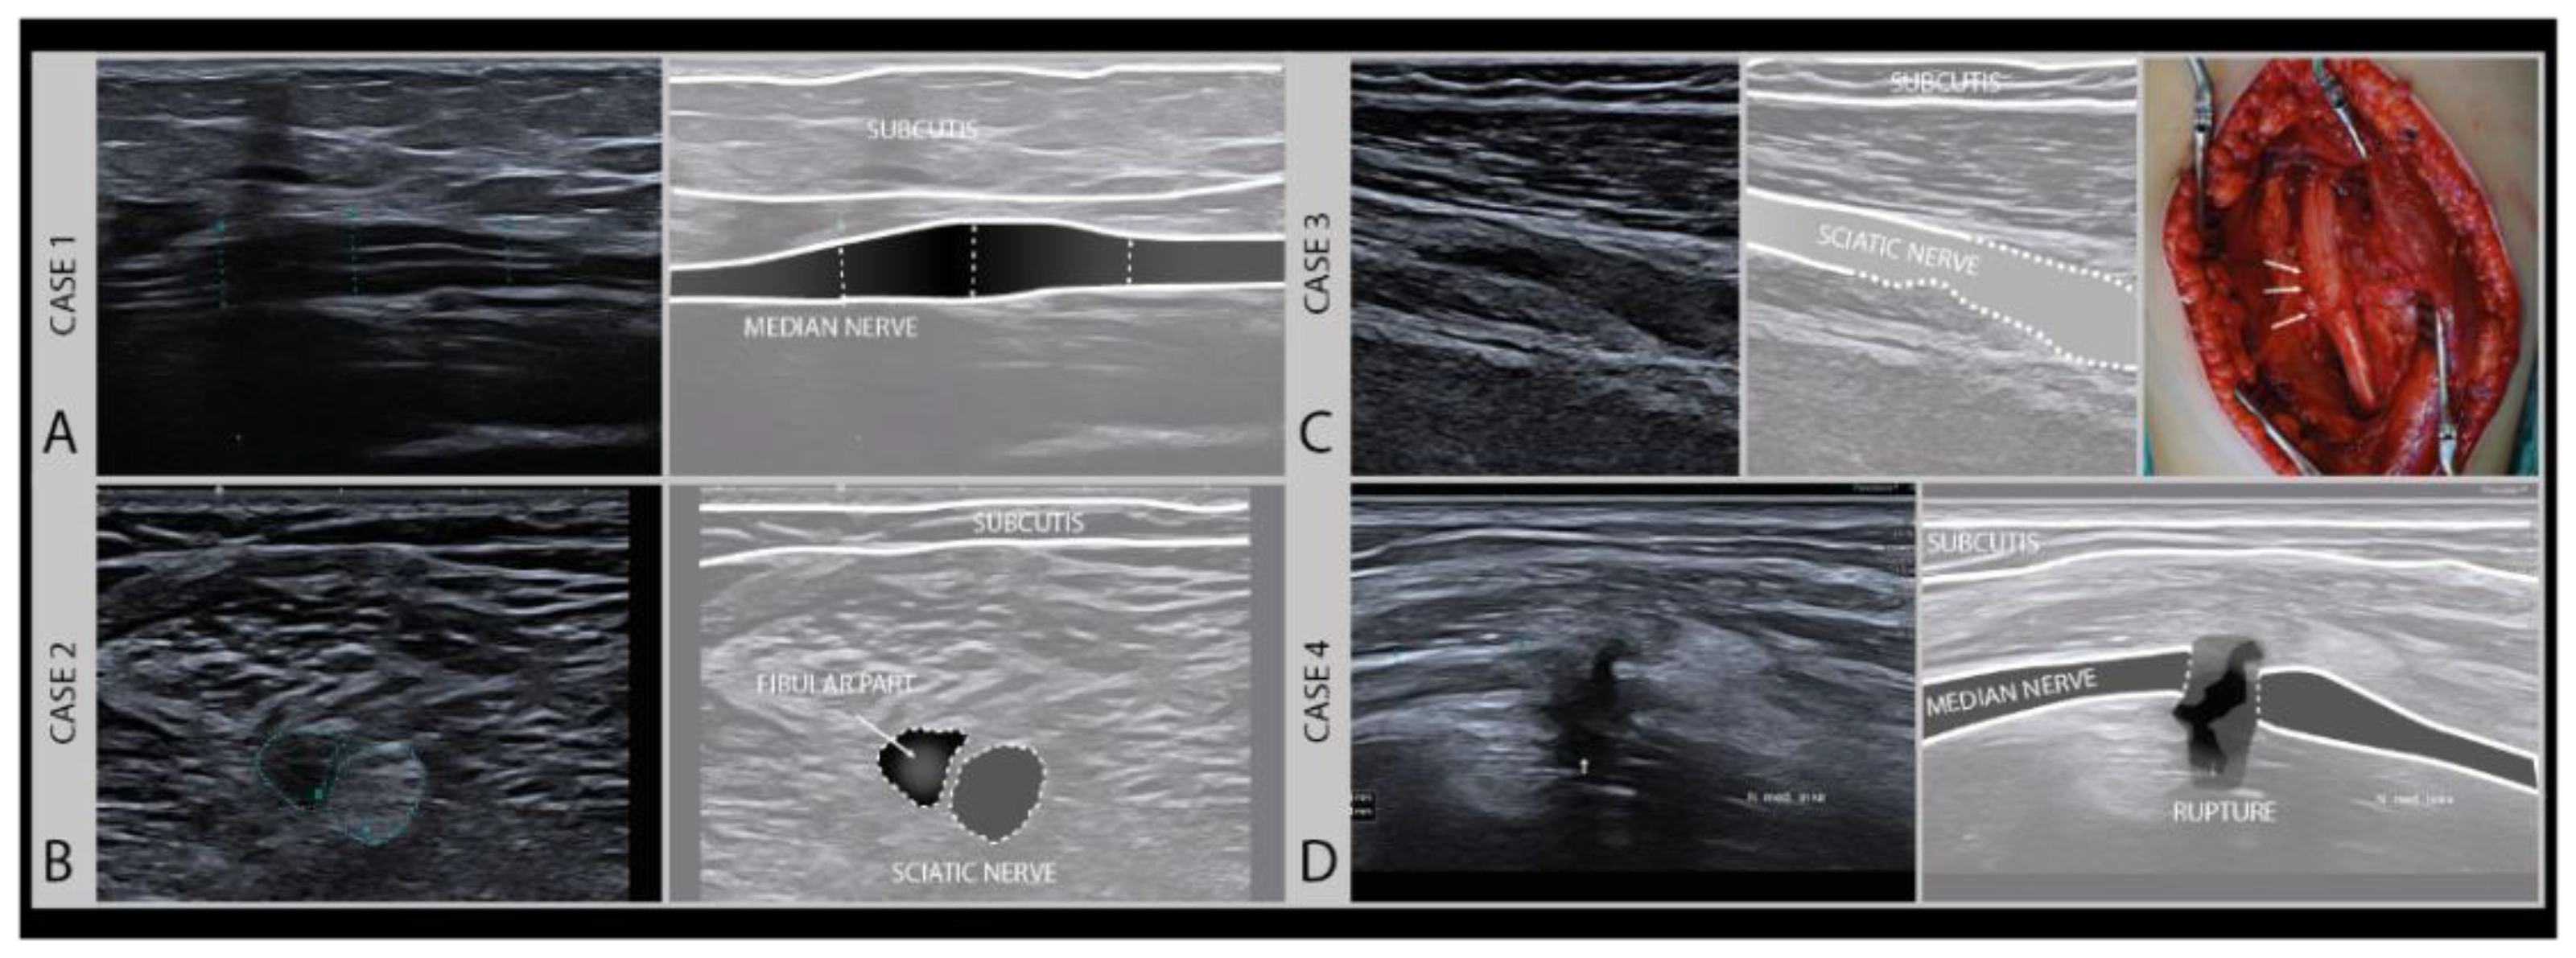

3.2. Assessing Nerve Continuity

An important aspect for choosing the right therapeutic procedure and thus influencing the prognosis of a nerve injury, is to differentiate between patients with higher Sunderland grade intraneural damage or even the transection of a nerve versus a less severe lesion with preserved nerve continuity and good regenerative potential. To categorize a lesion as major or minor based on imaging (Figure 6), a few typical sonomorphologic signatures can be used, that include the fascicle swelling and hypoechoity of the nerve, the absence of a normal fascicular pattern, and the continuity assessment to detect partial or complete nerve severance with the presence of neuronal stump [28,29].

Figure 6.

Examples of different degrees of axonal damage. Case 1 (A): median nerve swelling following local trauma (fracture), fascicles intact, full recovery without surgery (Sunderland II). Case 2 (B): heterogeneous lesion of the sciatic nerve (peroneal part) of a 19-year-old boy after a scooter accident. Case 3 (C): sciatic nerve damage (Sunderland III) in a 9-year-old girl after a severe car-accident (high-frequency 9–18 MHz). (Intraoperative image kindly provided by PD. Dr. F. Lassner). Case 4 (D): iatrogenic median nerve lesion with loss of nerve continuity (Sunderland V) in a 53-year-old man after arthroscopy of the elbow joint (high frequency 19–24 MHz).

In pure neurapraxia, a Sunderland grade 1 and the least severe lesion, there are either no pathologic findings on ultrasound or just a mild swelling of the nerve with an intact fascicular pattern. A Sunderland grade 2 injury is slightly more severe with axonal damage, and also shows clearly enlarged cross-sectional areas of affected fascicles and nerves at the lesion site because of axonal swelling and edema. Higher grade damage like in patients with Sunderland grade 3 and 4 lesions shows a loss of the normal nerve architecture and echotexture with a disruption of the fascicular pattern and often sizeable hypoechogenic enlargement of the nerve. The more extensive the loss of the normal nerve architecture, the higher the chance that the nerve will develop intraneural fibrosis that hampers or prohibits recovery. For these lesions, a subdivision of the Sunderland system has been described by Millesi [30]. A Sunderland grade 5 lesion shows a transection of the nerve with a loss of nerve continuity. An overview of the nerve injury classification can be found here: https://en.wikipedia.org/wiki/Peripheral_nerve_injury_classification.

The early identification of these Sunderland grade 4 and 5 lesions is very important for predicting the outcome and the need for surgery [21,22]. High-resolution ultrasound allows this early categorization of lesions to guide surgical decision making [31]. Surgery is always indicated if nerve continuity is lost (i.e., Sunderland grade 5). In the case of a complete transection, the proximal and distal nerve stump will be separated, and as the regenerating axons in the fascicles have no guiderail for regrowth, they will form a stump neuroma as they sprout. A similar situation can occur if there is no gap, but so much intraneural damage that the nerve forms an internal “wall“ of fibrosis (i.e., Sunderland grade 4), through which axons cannot regrow (also see below). This will result in a large disorganized swelling at the lesion site, described as a neuroma in continuity.